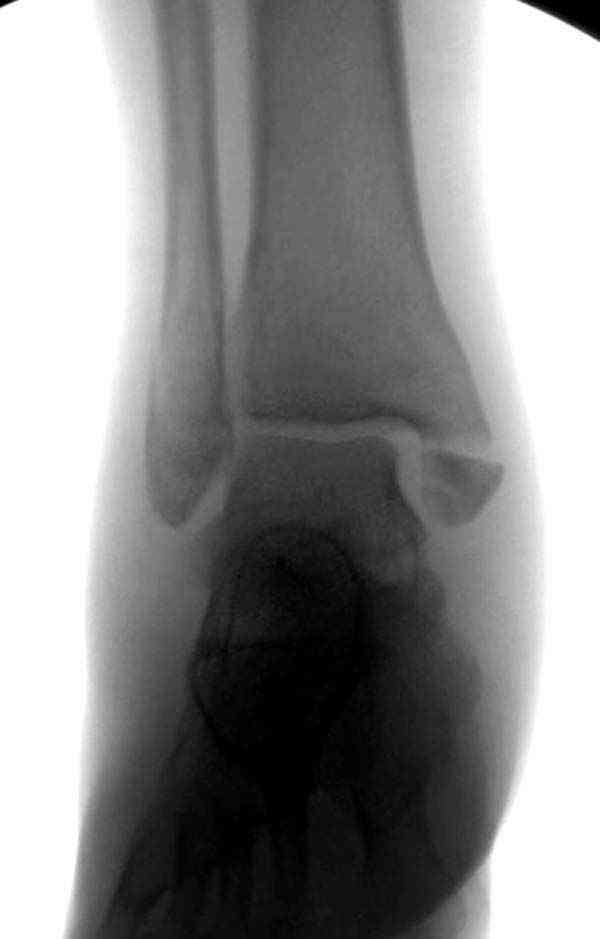

Добрый вечер, коллеги! Хотелось бы увидеть стандартные проекции, прямо, боком и мортиз. Дело скорее всего не в пластине. Стяжка скорее всего не дотянута изначально. Отсюда игра синдесмоза и прорезывание проволоки Вебера. Вообще то стоило бы делать по классике , а именно : Наружная лодыдка - противоскользящая плата по Веберу, над синдесмозом - два позиционных винта ( это "ключи" сустава) внутренняя лодыжка - можно и проволокой, но при адекватной фиксации латерального комплекса.

Раз ,есть желание посмотреть другую проекцию выкладываю-ну лучшего качества нет...

Отдельное спасибо,всегда с удовольствием читаю Ваши комментарии-всегда подробные и наглядные.К сожалению,не всегда применимы к нашим убогим условиям.Первичных снимков нет-просто банальный перелом с подвывихом,правда уже срастающийся(я не фотографировал их,а потом уже не стал искать в архиве).Не совсем понятно-"под большим сомнением разрыв синдесмоза"(с).Перелом пронационный с инверсией и как следствие ,ротацией лодыжки.То есть по сути было повреждение(разрыв) только передней порции,при сохраненной задней и межкостной мембране.В таком случае диагноз "разрыв синдесмоза"правомерен?